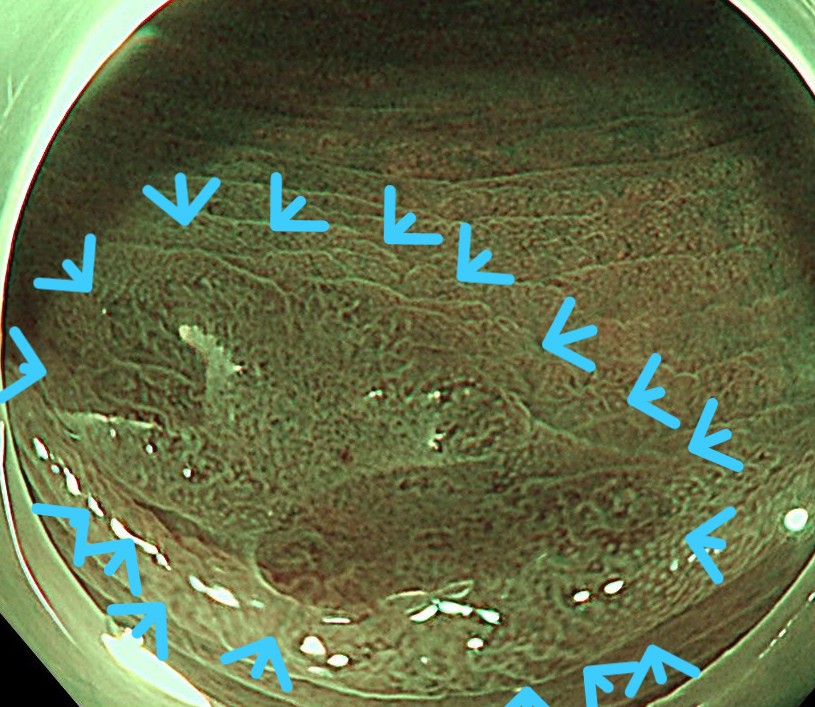

狭帯域光観察 (NBI) にて境界明瞭なIIA+IIC lesionとしてとらえられます。

NBI弱拡大観察しますと、周囲はピットIII型が中心ですが、陥凹部はIV~V型を呈します。